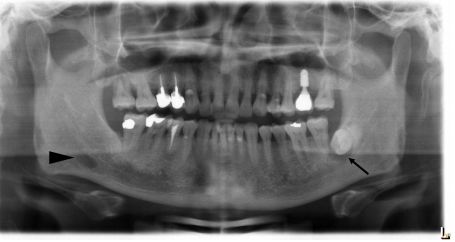

55.如全口環狀X光片所示,下顎骨左側可以發現多房性(multilocular) 放射線透光性病灶,並呈現有多顆牙齒之 牙根吸收,下列何者是較為可能之診斷? (A)鈣化齒源囊腫(calcified odontogenic cyst) (B) 含齒囊腫(dentigerous cyst) (C)齒源性角化囊腫(odontogenic keratocyst) (D)始基囊腫(primordial cyst)

66.15歲女孩丙下顎前方有一個無疼痛的腫脹而來求診,經X光檢査如附圖所示,病變區切片後,病理診斷為齒 源性角化囊腫,則此病患最可能罹患下列何種疾病? (A)艾迪森氏病(Addison's disease) (B)天使症(cherubism) (C)麥克滾-阿爾布萊德氏症候群(McCune-Albright syndrome) (D)痣樣基底細胞癌症候群(nevoid basal cell carcinoma syndrome)